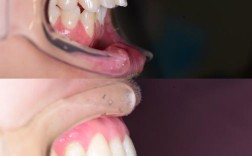

牙齿排列不齐、咬合异常等问题在儿童中较为常见,如“地包天”“龅牙”“牙齿拥挤”等,这些问题若不及时干预,可能导致一系列危害:一是影响咀嚼功能,降低食物消化吸收效率;二是增加龋齿、牙周病风险,因为错位牙难以清洁;三是可能影响发音,如“地包天”可能导致发音不清;四是对面部美观造成影响,导致孩子产生自卑心理,甚至影响社交发育,部分错颌畸形(如上颌前突、下颌后缩)还可能伴随颌骨发育异常,早期干预可引导颌骨正常生长,避免成年后需要正颌手术的复杂治疗。

- 乳牙期(3-5岁):主要针对乳牙反颌(“地包天”)、后牙反颌、口腔不良习惯(如吮指、咬唇、口呼吸)等,此阶段孩子颌骨可塑性强,通过简单矫正器(如活动矫治器)破除不良习惯,可引导上颌骨发育,避免下颌骨过度前伸。“地包天”若在乳牙期不干预,可能导致恒牙期反颌加重,甚至影响面部中份发育。

- 替牙期(6-10岁):这是“颌骨生长发育的快速期”,也是纠正功能性错颌的关键阶段,常见问题包括上颌前突(“龅牙”)、下颌后缩、个别牙反颌、牙列间隙异常等,此时可通过功能矫治器(如FRⅢ矫治器、Twin Block)刺激或抑制颌骨生长,改善上下颌骨关系,为恒牙排列创造空间。

- 恒牙早期(11-14岁):此时大部分恒牙已萌出,颌骨发育接近成熟,是进行固定矫正的“黄金时期”,主要解决牙齿拥挤、牙列稀疏、深覆合、深覆盖等问题,通过传统托槽矫正或隐形矫正排齐牙齿,调整咬合关系。